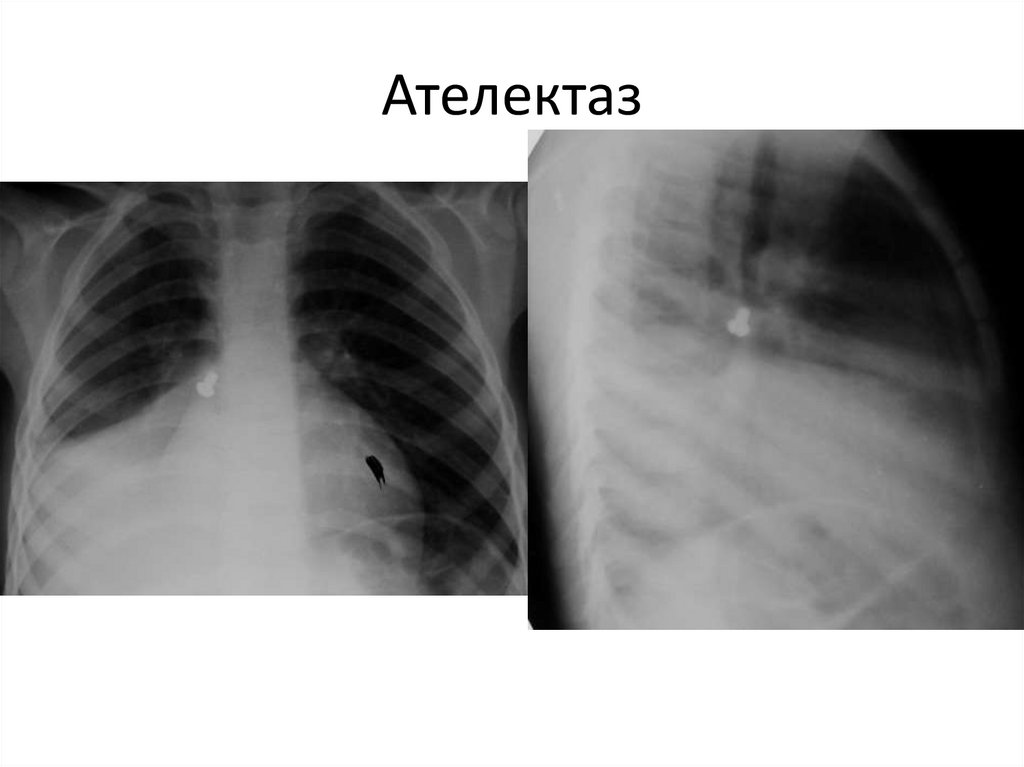

Ателектаз